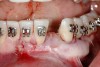

Figure 12  Right buccal view showing posterior occlusion established, canine guidance and proper space appropriation around peg lateral tooth No. 7, and intruded worn incisors.

Figure 12

This treatment plan was elected with the premise to reevaluate treatment options during orthodontic tooth movement. Soft-tissue augmentation was initiated to correct the mucogingival defect in the area of teeth Nos. 21 and 22. A free gingival graft was performed to achieve an adequate band of attached and keratinized gingiva to resist potential stripping on the root surfaces of teeth Nos. 22 and 21 during orthodontic movement (Figure 8). Orthodontic movement then was initiated to site-develop position No. 23 for an implant (Figure 9 through Figure 11). Orthodontics also was used to idealize the patient’s occlusion and develop canine guidance to minimize occlusal load and maximize the redistribution of forces36-40 for protecting the future implant from deleterious forces. The space was opened around the peg lateral tooth No. 7, and the gingival levels were aligned for maxillary incisors. Bonding was performed to restore the length of teeth Nos. 8 through 10 and to bond the peg lateral to a normal tooth form, which allows the orthodontist to idealize the posterior occlusal scene and maintain canine guidance (Figure 12 through Figure 13).